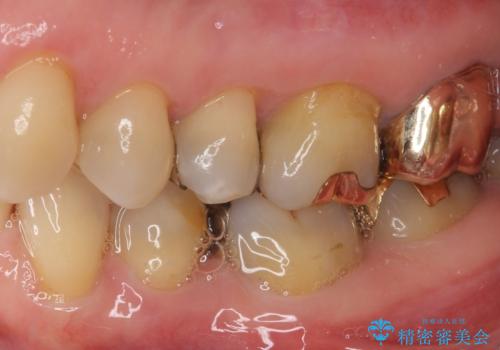

外れてしまった銀歯 セラミックインレーで自然な仕上がりに

- 奥歯の銀歯が外れてしまったため、セラミック治療を希望された患者様です。

セラミックインレーによる修復治療を実施しました。

正面から見える場所であったため、セラミックインレーで自然な口元にすることができました。